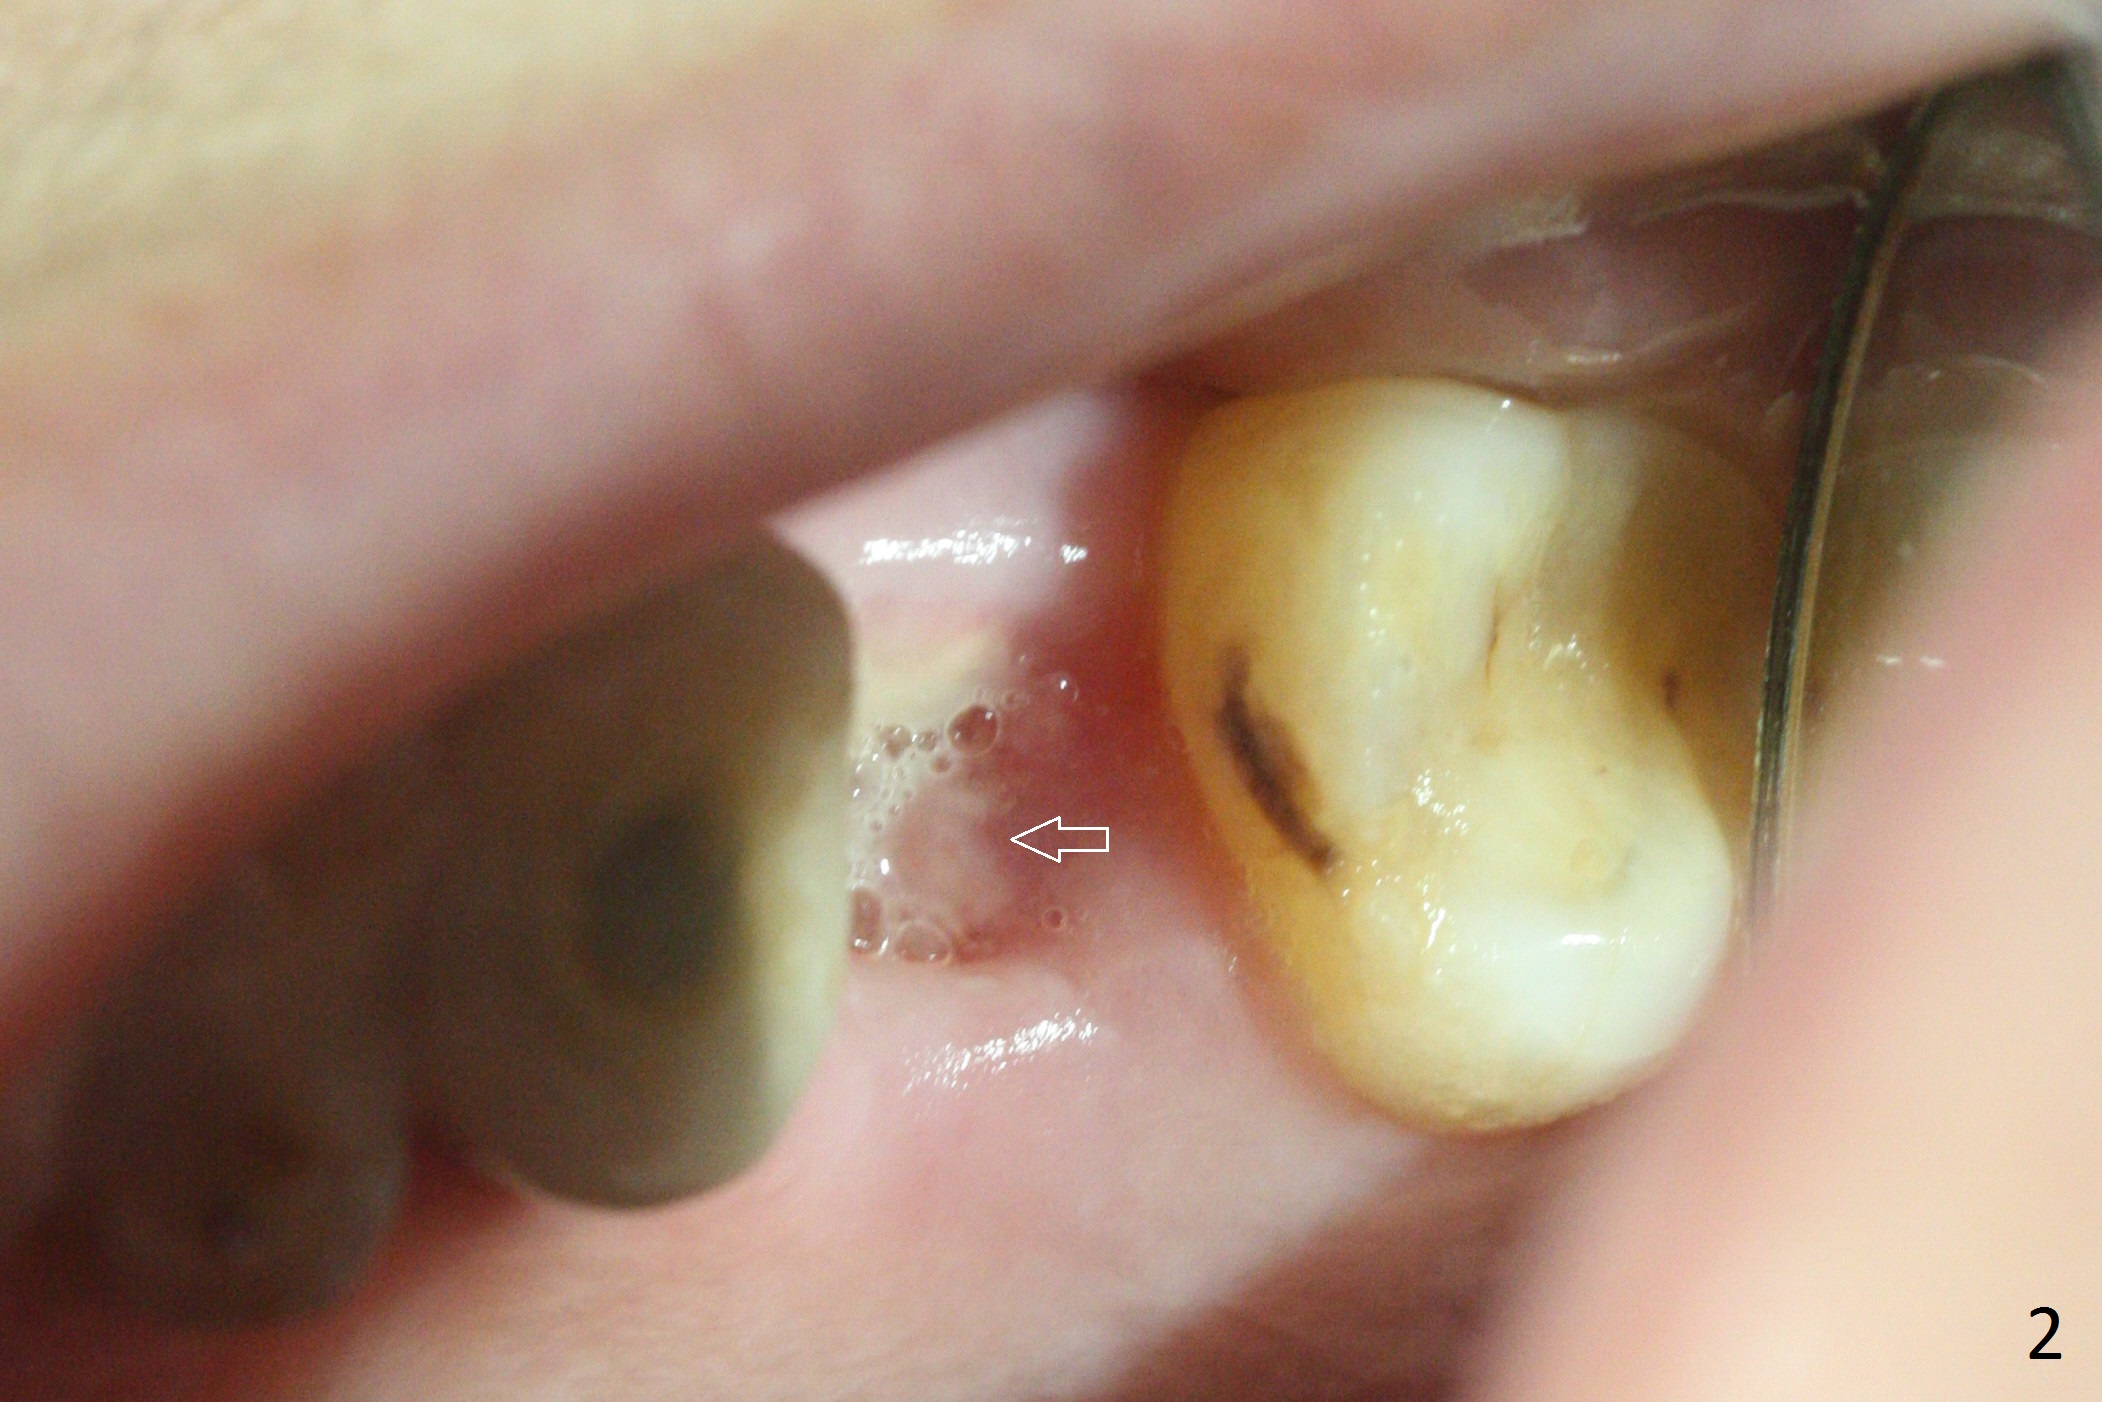

A 61-year-old woman has pain after RCT at #14 (Fig.1). Exam shows subgingival crack. After difficult extraction, allograft with Osteogen is placed in the 3 sockets, followed by Osteogen plug and 4-0 Chromic Gut Suture. The distal gingiva appears to be migrating into the center of the sockets (Fig.2 arrow). Due to insurance issue, an implant will be placed early next year. The patient returns 9 months post extraction (Fig.3). If the ridge proves to be not so wide, make incision, start osteotomy with 1.6 mm pilot drill, followed by 4.3 mm Magic Drill for 7 mm and 3.8 mm Magic Expander for another 2 mm (sinus lift, BEB, Fig.4). Otherwise start Magic Split. If the bone is dense, use drills and Expander as mentioned above with the depths 2 mm more (Fig.5), followed by Magicore. The tissue-level implant improves the crown/implant ratio over the FC. After socket healing, gingival cuff height is stable. The cuff of Magicore is easy to determine vs. immediate case.